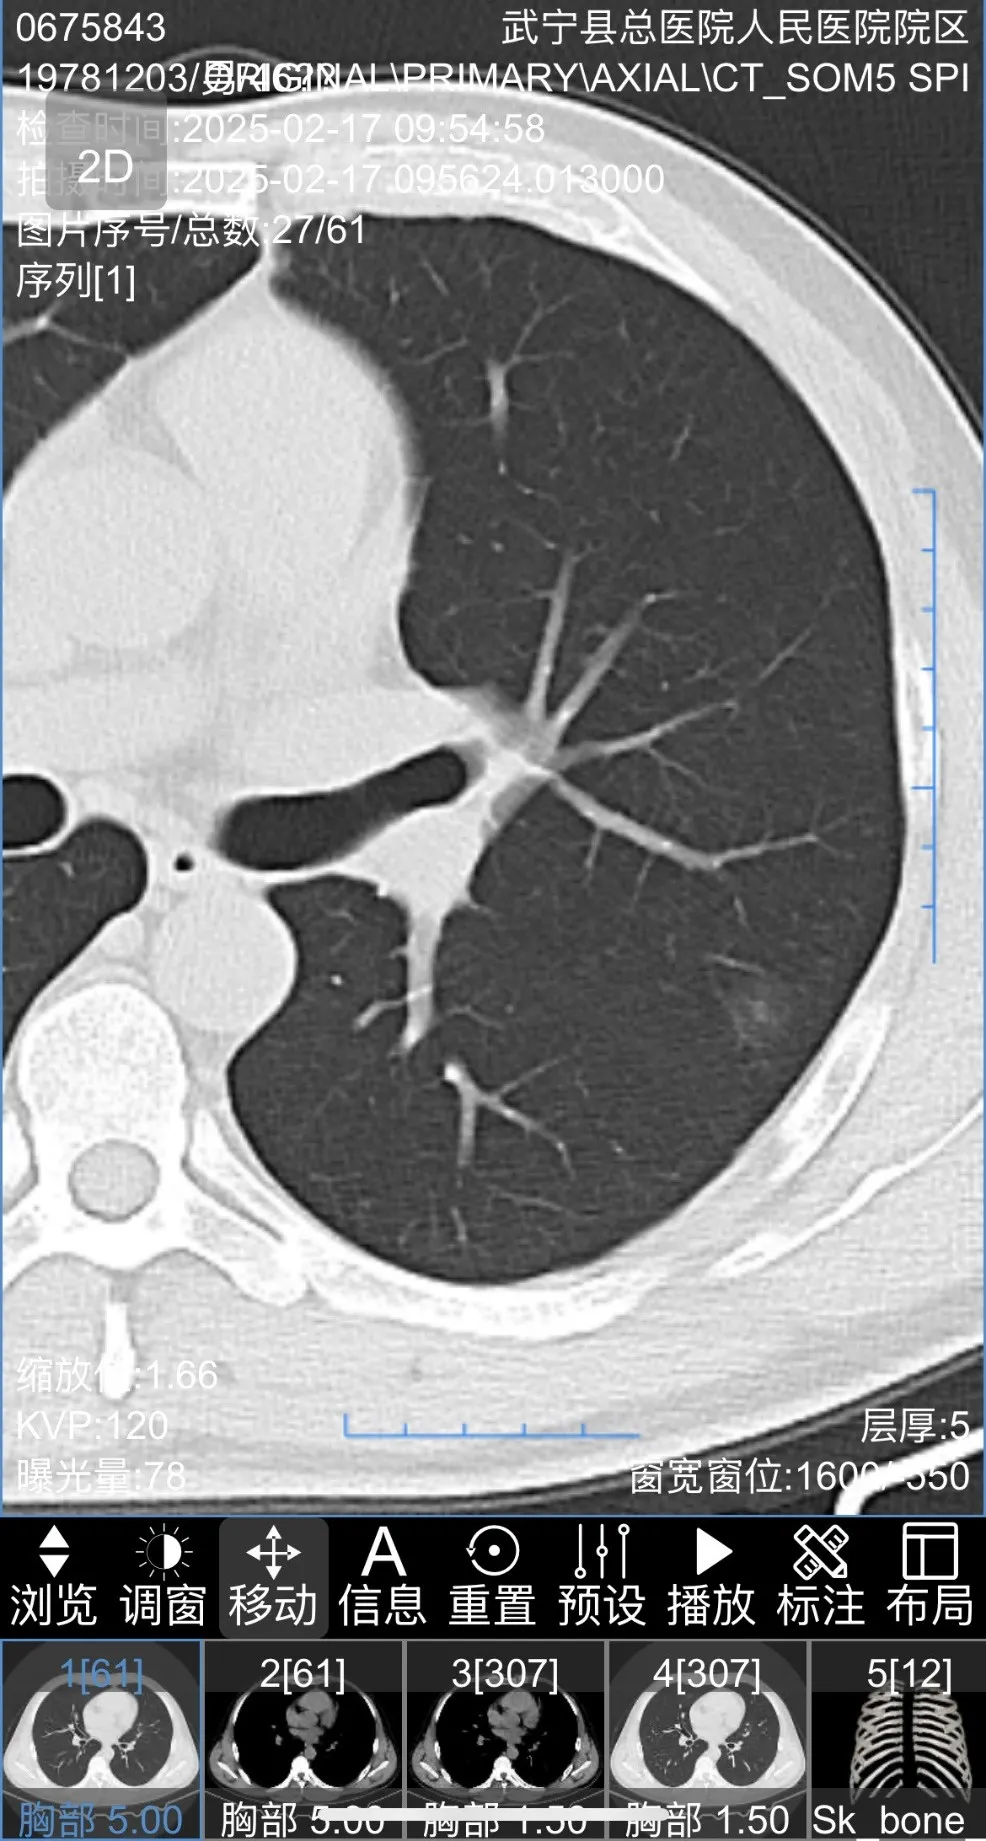

患者胸部(bù)CT圖片如下